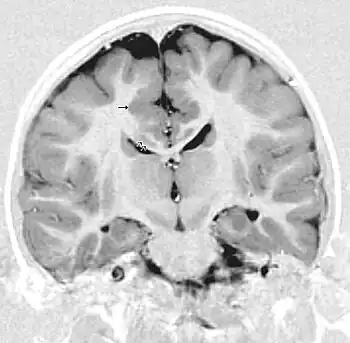

Periventricular or subependymal

Periventricular means beside the ventricle, while subependymal (also spelled subepydymal) means beneath the ependyma; because the ependyma is the thin epithelial sheet lining the ventricles of the brain, these two terms are used to define heterotopia occurring directly next to a ventricle. This is by far the most common location for heterotopia. Patients with isolated subependymal heterotopia usually present with a seizure disorder in the second decade of life.

Subependymal heterotopia present in a wide array of variations. They can be a small single node or a large number of nodes, can exist on either or both sides of the brain at any point along the higher ventricle margins, can be small or large, single or multiple, and can form a small node or a large wavy or curved mass.